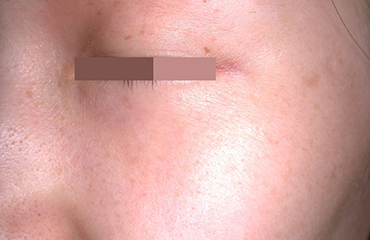

기미

기미는 서서히 발생하여 보통 대칭적으로 생긴다.발생 시기는 대개 사춘기 이후이며, 남자에게도 생기지만 대부분 여자에게서 발생한다.

여름에 진해지고 겨울에 흐려지며 광대뼈 부위나 얼굴의 가운데 혹은 턱선을 따라 잘 생긴다.

• 기미 시술 전

• 기미 시술 후